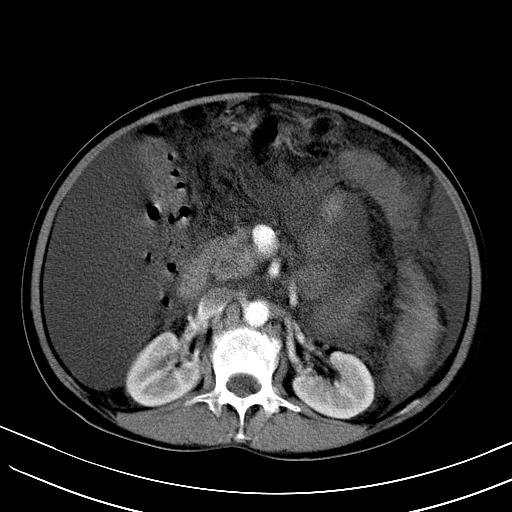

1)肝右叶肝癌并肝动静脉漏。2)肝硬化,腹水。3)胆囊炎。

肝右叶肝癌并动静脉漏,肝硬化,腹水。

1)肝右叶肝癌并肝动静脉漏 门v右支瘤栓伴海绵样变。2)肝硬化,脾大 腹水。3)胆囊炎。门v高压.

右叶肝癌并肝动静脉漏(动脉期肝动脉及门静脉内均可见造影剂),肝硬化,腹水。(胆囊壁水肿)

1)肝右叶肝癌,考虑并发肝动静脉漏。扫描时间好像慢了。2)肝硬化,门脉高压、脾大、腹水。